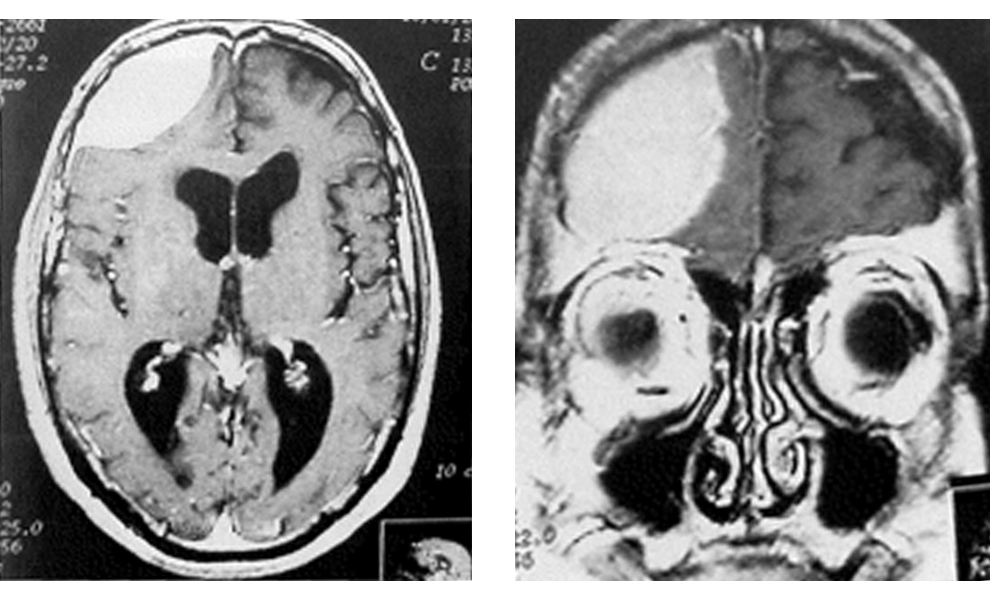

Εικόνες 1α,1β. Παροβελιαίο μηνιγγίωμα της κυρτότητας, δηλ. κοντά στη μεσότητα και κοντά στην επιφάνεια του εγκεφάλου και του κρανίου.